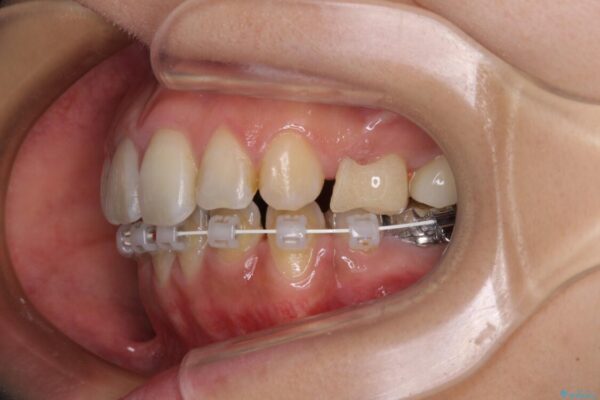

治療途中

• デコボコと口元の突出感 ハーフリンガルでの抜歯矯正 治療途中画像

前歯のデコボコと上顎の前突感による口の閉じにくさを気にして来院された患者様です。

目立たない装置を希望されたので、上顎が裏側装置のハーフリンガルを選択し、上下左右の小臼歯(計4歯)を抜歯して矯正治療を行うこととしました。